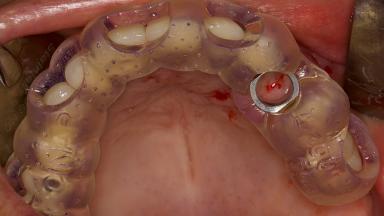

Digitally Guided Sinus Floor Elevation

In this short microlearning module on digitally guided sinus floor elevation, we delve into a specialized aspect of the digital workflow for implant-guided surgery, focusing on the use of digital guides in the sinus floor elevation technique.

- explore the intraoperative use of digital guides in SFE